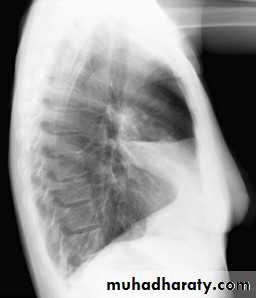

Right middle lobe collapse has distinctive features, and is usually relatively easily identified.

Radiographic features

Chest radiograph

Frontal chest XR showing opasity cause obscuration of the RT cardiac border

Lateral chest XR film the opacity is tongue like shape

versus (triangular in shape) in RT middle lobe consolidation seen in lateral chest XR film

RT middle lobe collapse